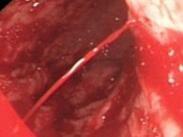

上消化道出血癥狀

• 上消化道出血

628健康網(wǎng)為您分享有關(guān)上消化道出血的癥狀,上消化道出血的治療方法,上消化道出血的預(yù)防知識,上消化道出血的癥狀圖片,上...